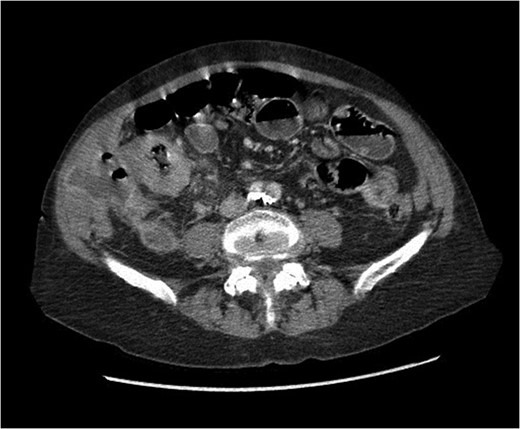

At presentation her vital signs were stable. Abdominal exam revealed exquisite tenderness in the right lower quadrant, with no evidence of digital clubbing. Blood-work revealed an elevated WBC of 15.6. A CT scan demonstrated a 4.3 cm annular mass within the cecum, suspicious for a primary colonic malignancy, as well as an 8.6 × 8.2 cm2 lobulated gas-containing abscess with extension in to the lateral abdominal wall (Figs 4 and 5).

Abdominal CT scan showing annular cecal mass with evidence of perforation.